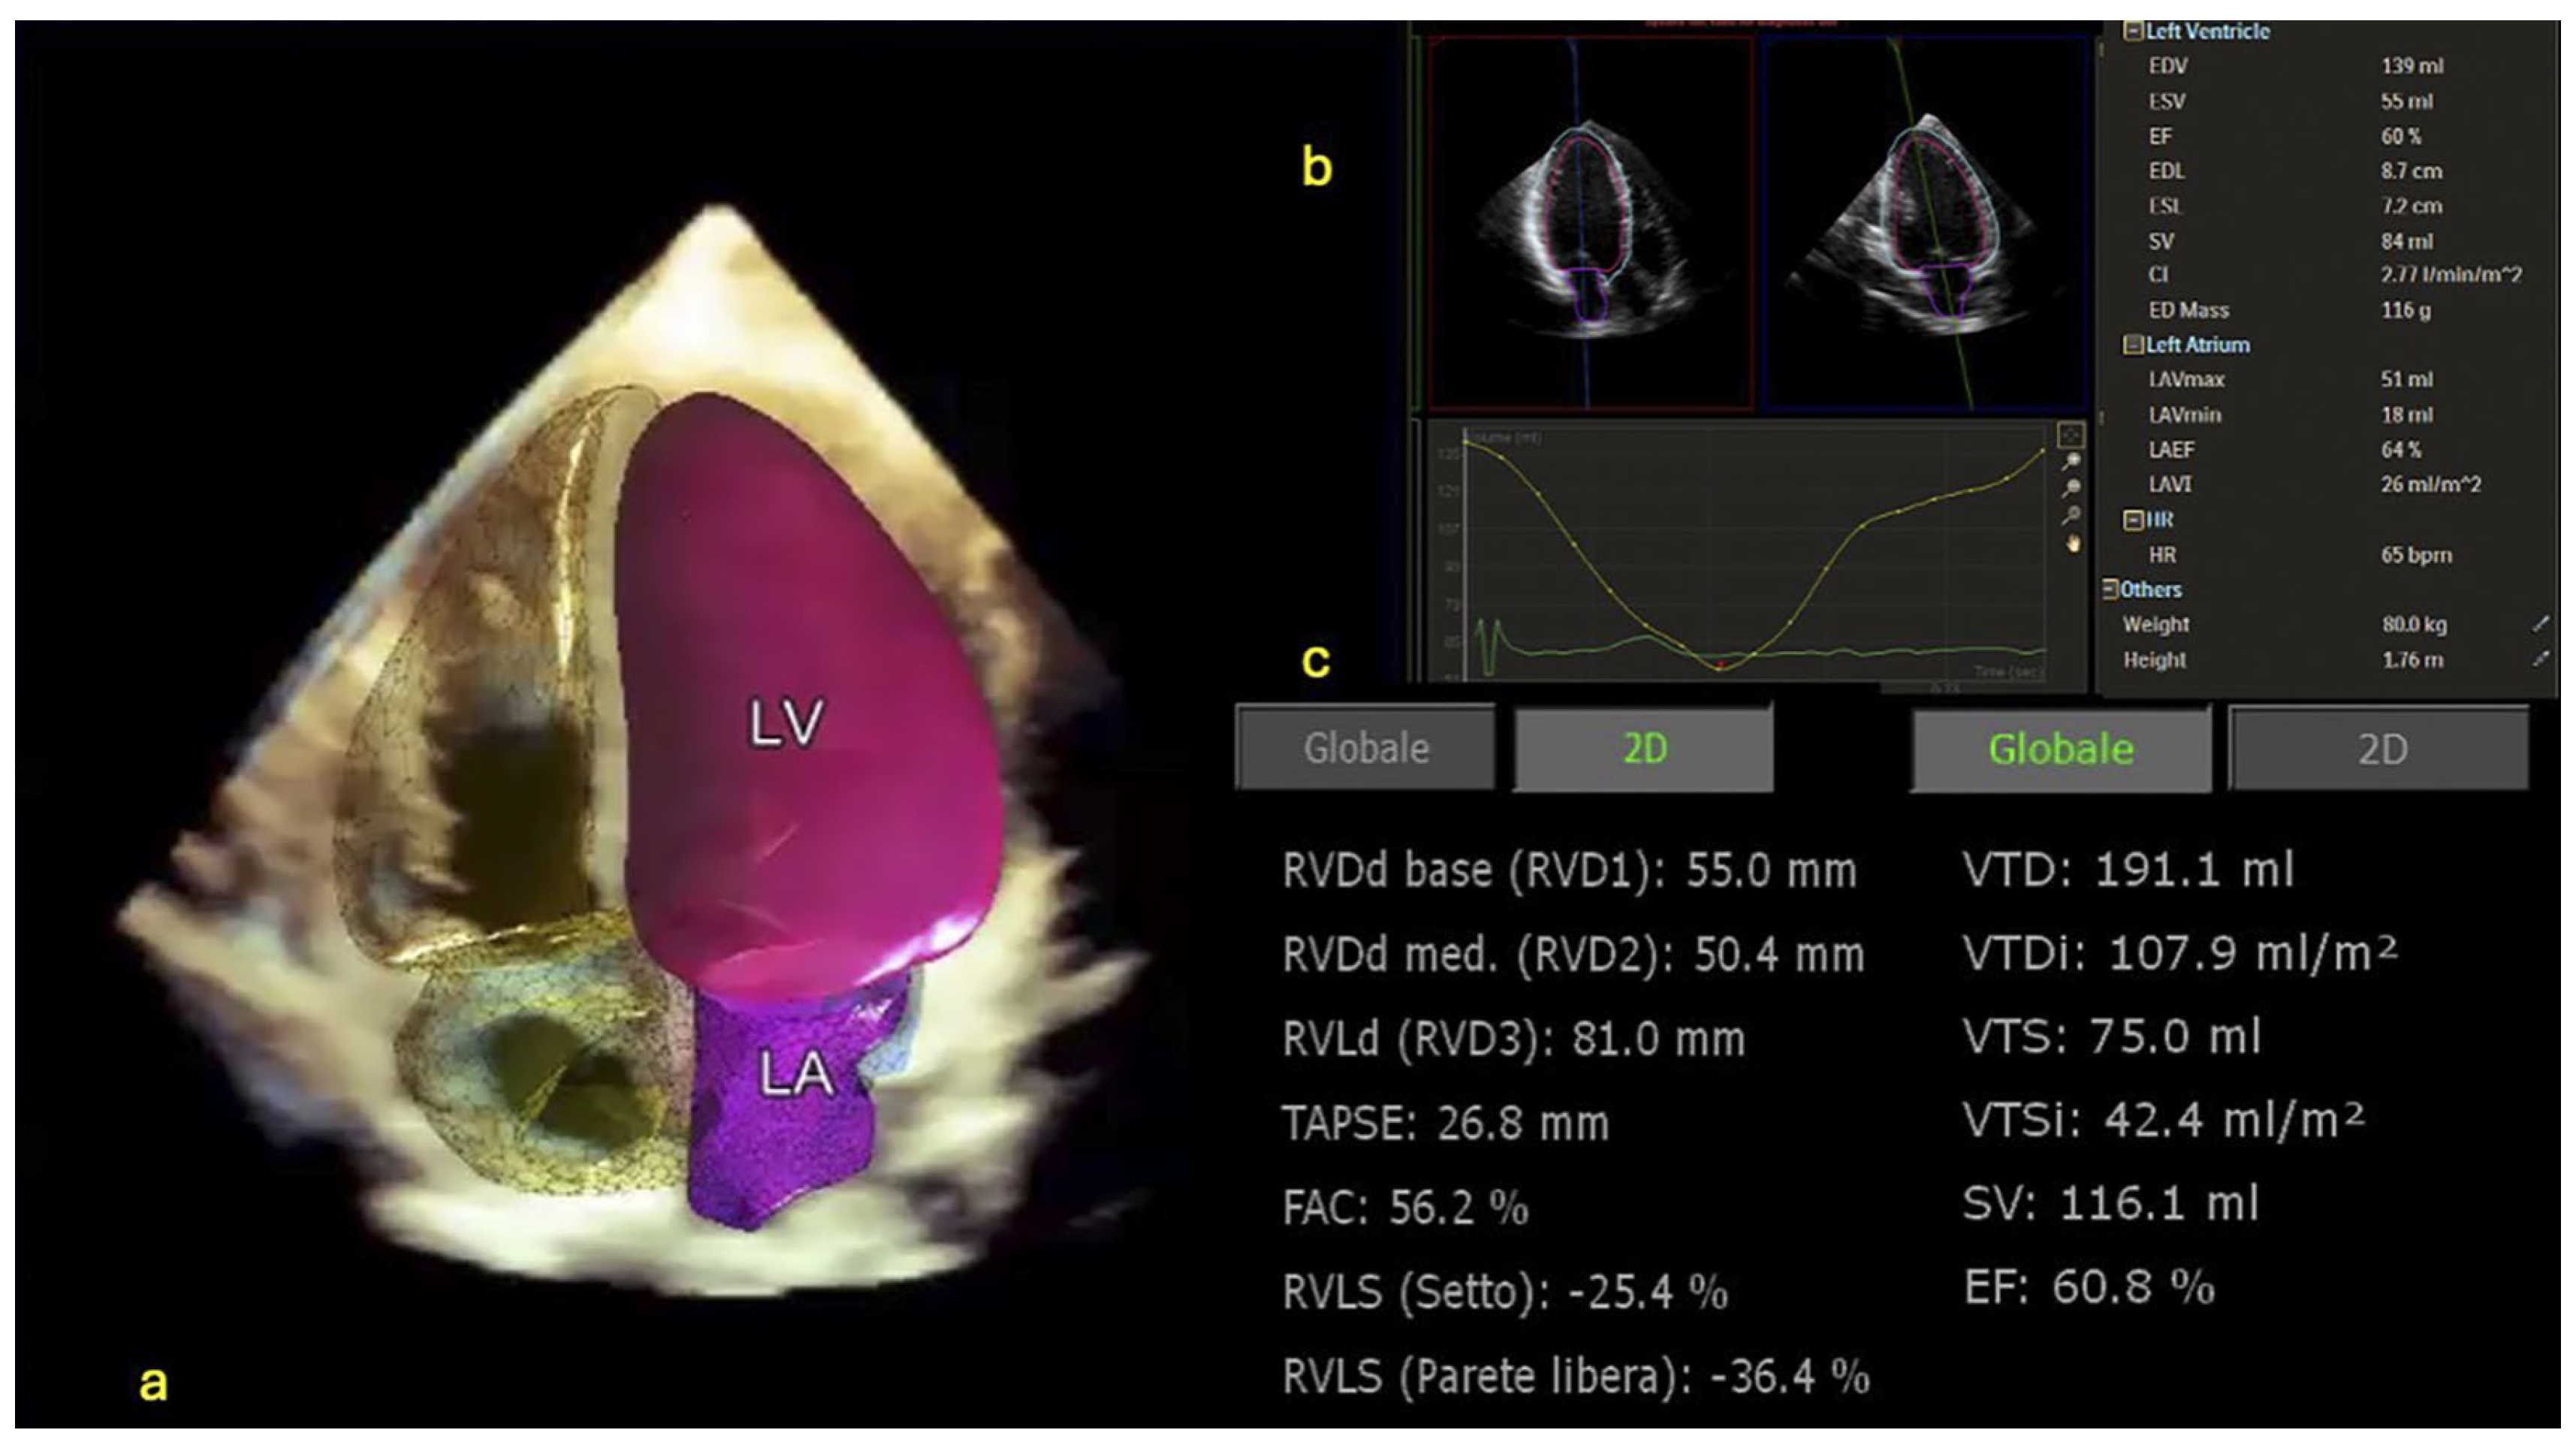

- Medvedofsky, D.; Mor-Avi, V.; Amzulescu, M.; Fernández-Golfin, C.; Hinojar, R.; Monaghan, M.J.; Otani, K.; Reiken, J.; Takeuchi, M.; Tsang, W.; et al. Three-dimensional echocardiographic quantification of the left-heart chambers using an automated adaptive analytics algorithm: Multicentre validation study. Eur. Heart J. Cardiovasc. Imaging 2018, 19, 47–58. [Google Scholar] [CrossRef] [PubMed]

| D. Medvedofsky et al. [39] | 2018 | Three-dimensional echocardiographic quantification of left-heart chambers | Automated adaptive analytics algorithm |